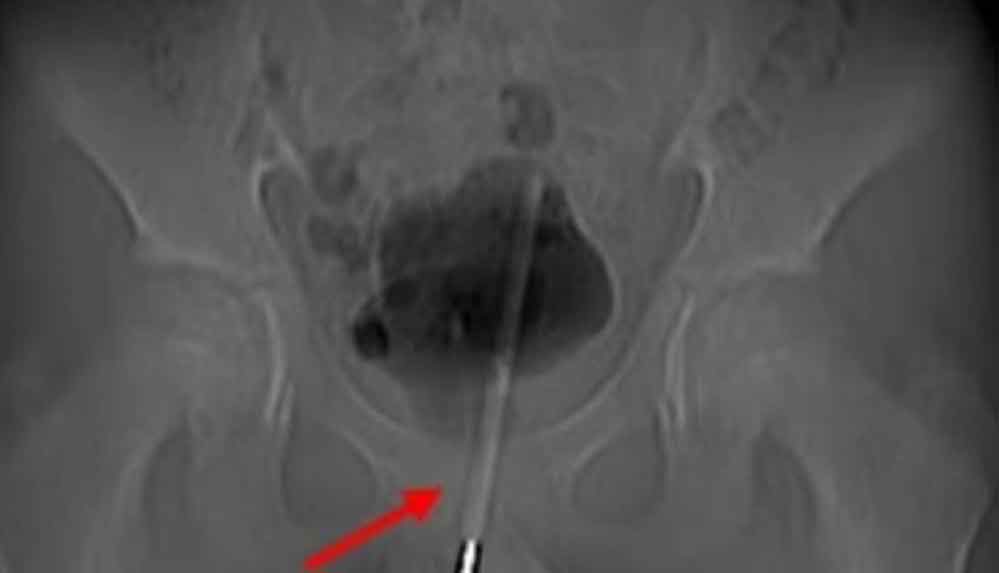

Çekilen röntgen, termometrenin idrar yoluna kadar sokulduğunu ve çocuğun mesanesine girdiğini ortaya çıkardı.

Asian Journal of Surgery’de vakayı detaylandıran ürologlar, mesaneye giden dokuda küçük bir cerrahi delik açtıklarını ve ardından termometreyi doğru konuma getirerek onu çıkarmak için küçük aletler kullandıklarını söylediler.